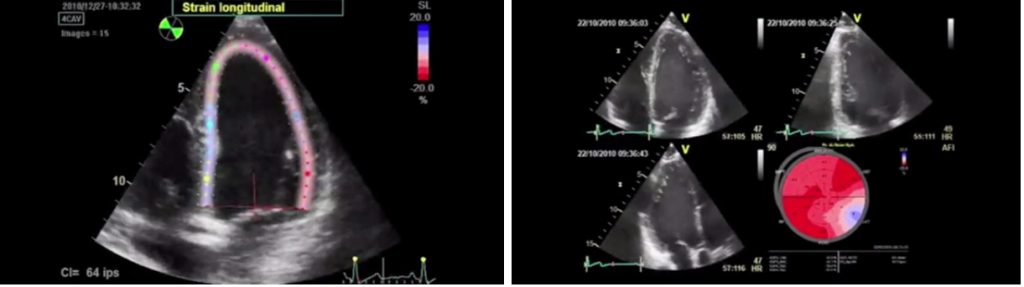

Измерение глобальной продольной деформации (global longitudinal strain или GLS)

Стоит отметить, что снижение фракции выброса левого желудочка – это достаточно позднее проявление кардиотоксичности, когда повлиять на ее исходы уже проблематично. Поэтому важной целью является ранняя диагностика доклинической дисфункции левого желудочка. И перспективным методом ранней диагностики кардиотоксичности является так называемая спекл-трекинговая эхокардиография, когда с помощью определенных программ исследуется так называемая глобальная продольная деформация миокарда. Относительное процентное снижение показателя, получаемого при измерении, более 15% от исхода считается патологическим и является признаком ранней доклинической дисфункции левого желудочка.

- При технической возможности использовать методы, позволяющие выявить раннюю субклиническую (доклиническую) дисфункцию миокарда и коррелирующие с последующим снижением ФВ ЛЖ (GLS или высокочувствительный тропонин I).

- При использовании GLS клинически значимым является снижение более чем на 15 % от исходной величины.